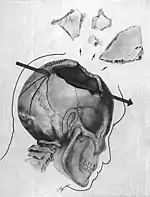

- The gunshot wound to the back of the president's head was described by the Bethesda autopsy as a laceration measuring 15 by 6 millimetres (0.59 in × 0.24 in), situated to the right and slightly above the external occipital protuberance. In the underlying bone is a corresponding wound through the skull showing beveling (a cone-shaped widening) of the margins of the bone as viewed from the inside of the skull.[38]

- The large and irregularly-shaped wound in the right side of the head (chiefly to the parietal bone, but also involving the temporal and occipital bone) is described as being about 13 centimetres (5.1 in) wide at the largest diameter.[38]

- Three skull bone fragments were received as separate specimens, roughly corresponding to the dimensions of the large defect. In the largest of the fragments is a portion of the perimeter of a roughly circular wound presumably of exit, exhibiting beveling of the exterior of the bone, and measuring about 2.5 to 3.0 centimetres (0.98 to 1.18 in). X-rays revealed minute particles of metal in the bone at this margin.[38]

- Minute fragments of the projectile were found by X-ray along a path from the rear wound to the parietal area defect.[39]